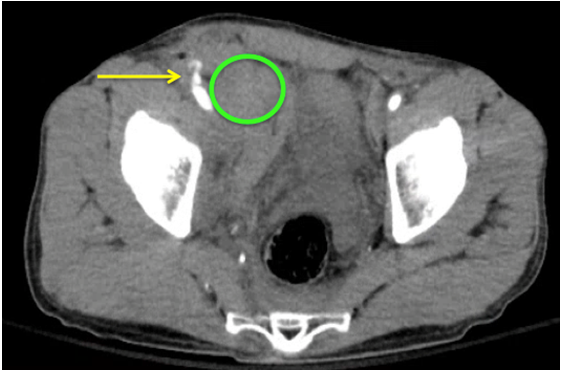

Answer: Active extravasation from R iliac artery w/ large retroperitoneal hematoma

- In image above- Yellow arrow shows active extravasation, while green circle shows developing RP hematoma

- Retroperitoneal hematoma formation is a rare but serious complication of femoral artery catheterization

- Symptoms may include: groin pain/tenderness, severe back pain or lower quadrant abdominal pain, or femoral neuropathy

- Any anticoagulation should be reversed

- Patient should be resuscitated with blood products early

- Surgical emergency requiring prompt operative repair- immediate consult to vascular surgery/IR depending on resources available